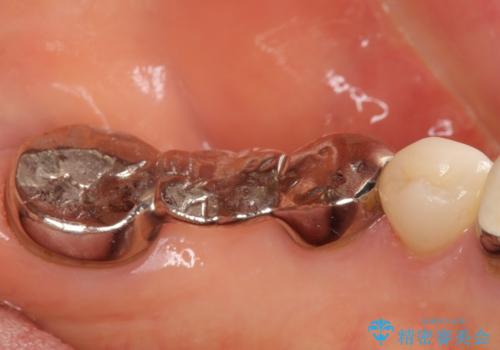

清掃しづらく、見た目の気になるブリッジ

- 毎回食事のたびに食べかすがつまり、見た目も気になる銀歯のブリッジやりかえを希望され来院されました。

精度の高いジルコニアブリッジの製作に加え歯茎にぴったりとそわせたオベイトポンティック形態とすることで清掃性・審美性に優れたブリッジを製作します。

歯ぐきの形態にそわせ、凸型でくぼみのないオベイト型のポンティックはプラークの溜まりにくく審美性も達成できるポンティック形態です。